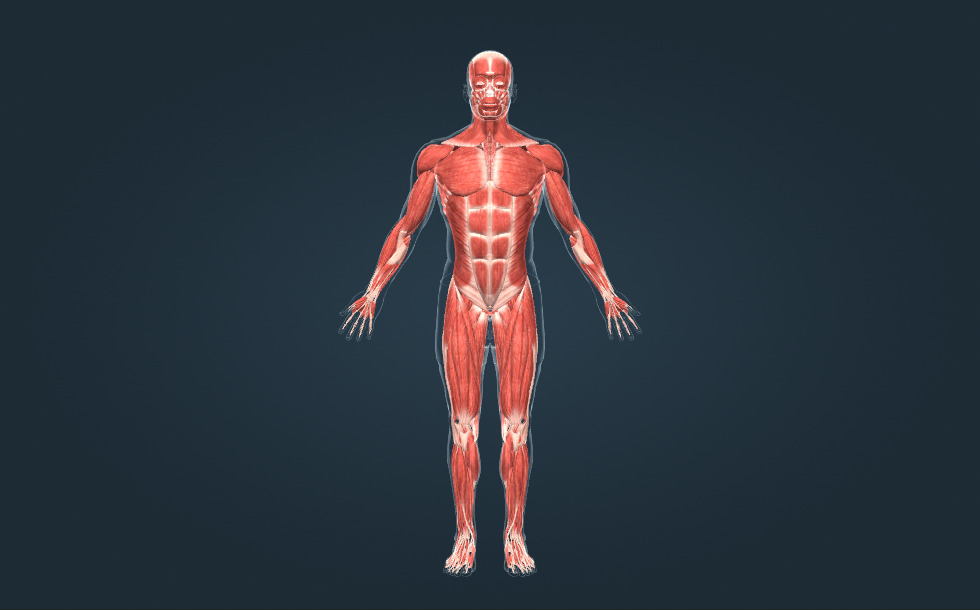

Σκελετικοί μύες

- μύες της κεφαλής

- μύες του στέρνου

- κοιλιακοί μύες

- μύες της κνήμης

- μύες του λαιμού

- μύες του άνω άκρου

- μύες του κάτω άκρου

- μύες του μηρού

- μύες της πλάτης

Οι σκελετικοί μύες είναι τα ενεργά όργανα της κίνησης. Υπάρχουν περίπου 350 σκελετικοί μύες στο ανθρώπινο σώμα, που αποτελούν περίπου το 50% της σωματικής μάζας. Υπάρχουν μακριοί, μικροί, επίπεδοι και δακτυλιοειδείς μύες. Οι μύες συνδέονται με τα οστά από τους τένοντες.

Οι σκελετικοί μύες είναι τα ενεργά όργανα της κίνησης. Υπάρχουν περίπου 350 σκελετικοί μύες στο ανθρώπινο σώμα, που αποτελούν περίπου το 50% της σωματικής μάζας. Υπάρχουν μακριοί, μικροί, επίπεδοι και δακτυλιοειδείς μύες. Οι μύες συνδέονται με τα οστά από τους τένοντες.